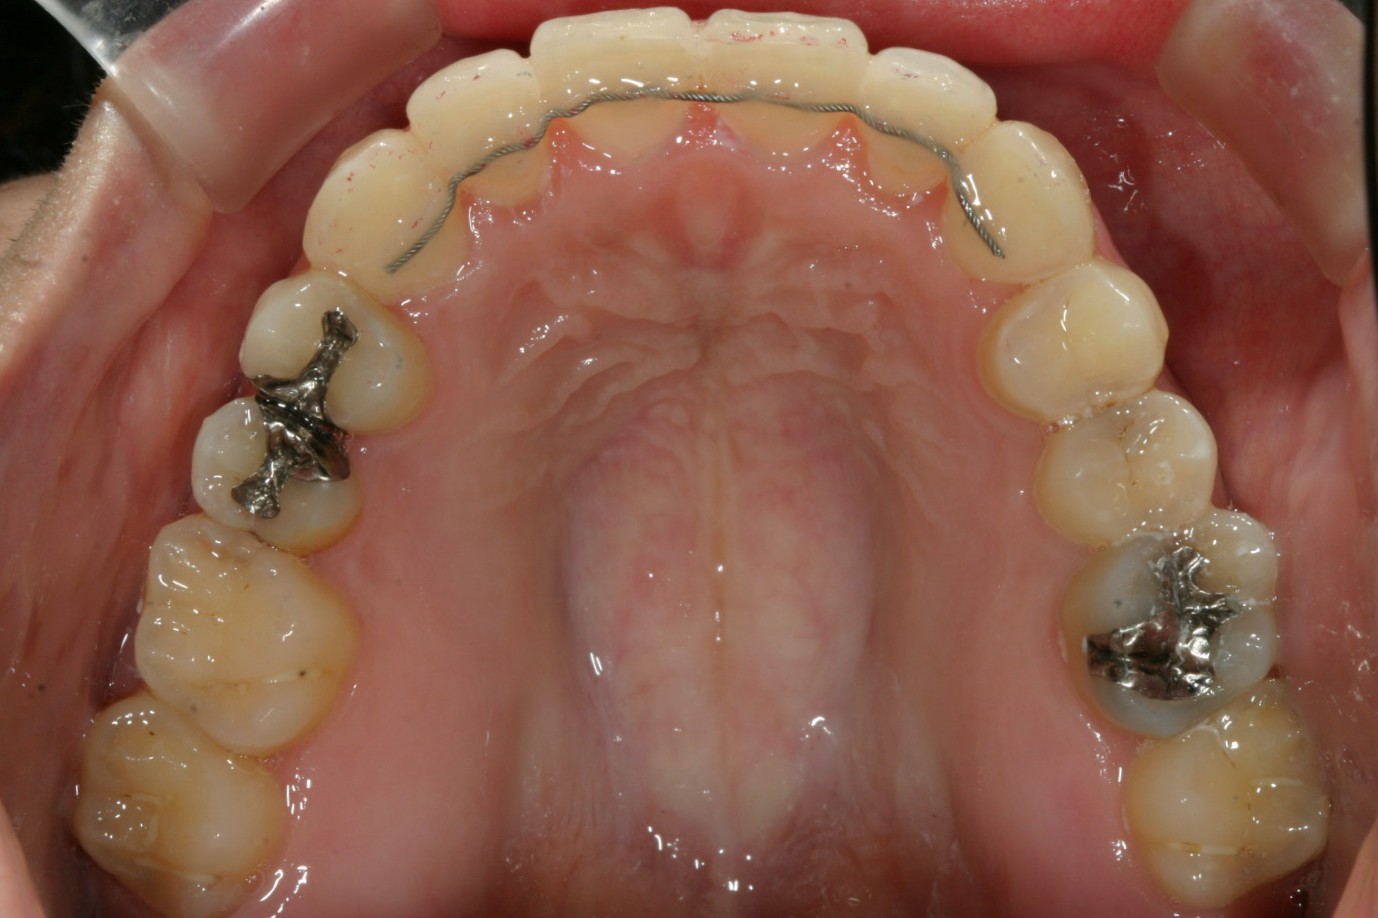

アーチを広げ綺麗に改善しました。

術前と比べると少しオーバージェットが増しました。

今回のケースも叢生ではよくあるケースで歯列弓が全体的に狭くなり結局そのしわ寄せが前歯に来て叢生になっています。

いつも通りアーチの拡大とIPR(歯と歯の間を少し削る)によりガタガタを取り又出っ歯を改善します。